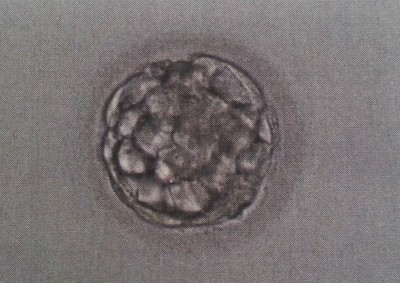

9 !!! Blastos